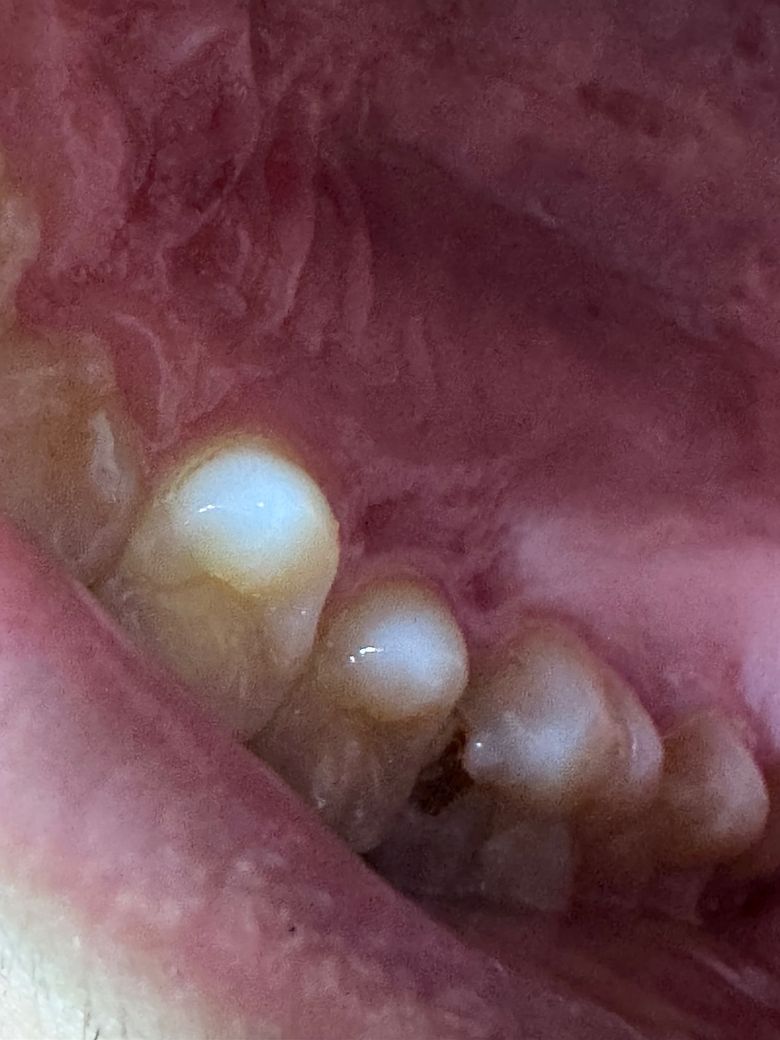

충치 이정도면 어느정도 상태인걸까요..? 금요일날 치과를 가는데 미리 어느정도 알아두고 가고싶어서 여쭈어봅니다! 사진만으로는 예상이 힘들겠지만 마음의 준비를 위해서 대략적으로라도 부탁드립니다..!! 그리고 치료는 어떻게 하게 될지도 알려주시면 감사하겠습니다!(레진치료가 가능할지..등등)

증상은 음식을 저 충치쪽으로 씹으면 아프긴합니다 ㅠㅠ 물이나 뜨거운것을 먹을때는 아프지는 않은데 저기 부분으로 음식을 씹을때만 통증이있어요!!

옆면이 꽤 썩은 상태이기 때문에 신경치료 가능성도 있습니다 다행히 신경치료는 안하더라도 레진으로는 어렵고 인레이를 해야할 수도 있습니다

충치가 많이 진행된 것으로 보이며, 이정도는 신경치료하고 씌우는 크라운 치료까지 해야 할 가능성 높습니다.

안녕하세요. 김지훈 치과의사입니다. 해당 충치쪽으로 씹으면 아픈 정도라면 신경치료나 크라운치료 등이 필요할 것으로 예상됩니다.

엑스레이를 찍어봐야 정확히 알겟지만 충치가 상당히 많이 진행된거 같으니 치과에 가셔서 신경치료를 하셔야될 가능성이 높아 보입니다.

음식을 먹을 때 통증이 있다면 해당 부위의 충치가 신경까지 진행되었을 가능성이 높습니다. 충치를 제거했을 때 신경이 노출이 된다면 신경치료에 가능성이 있으며 신경치료를 하게 되면 보철 치료를 해야 할 수 있습니다.